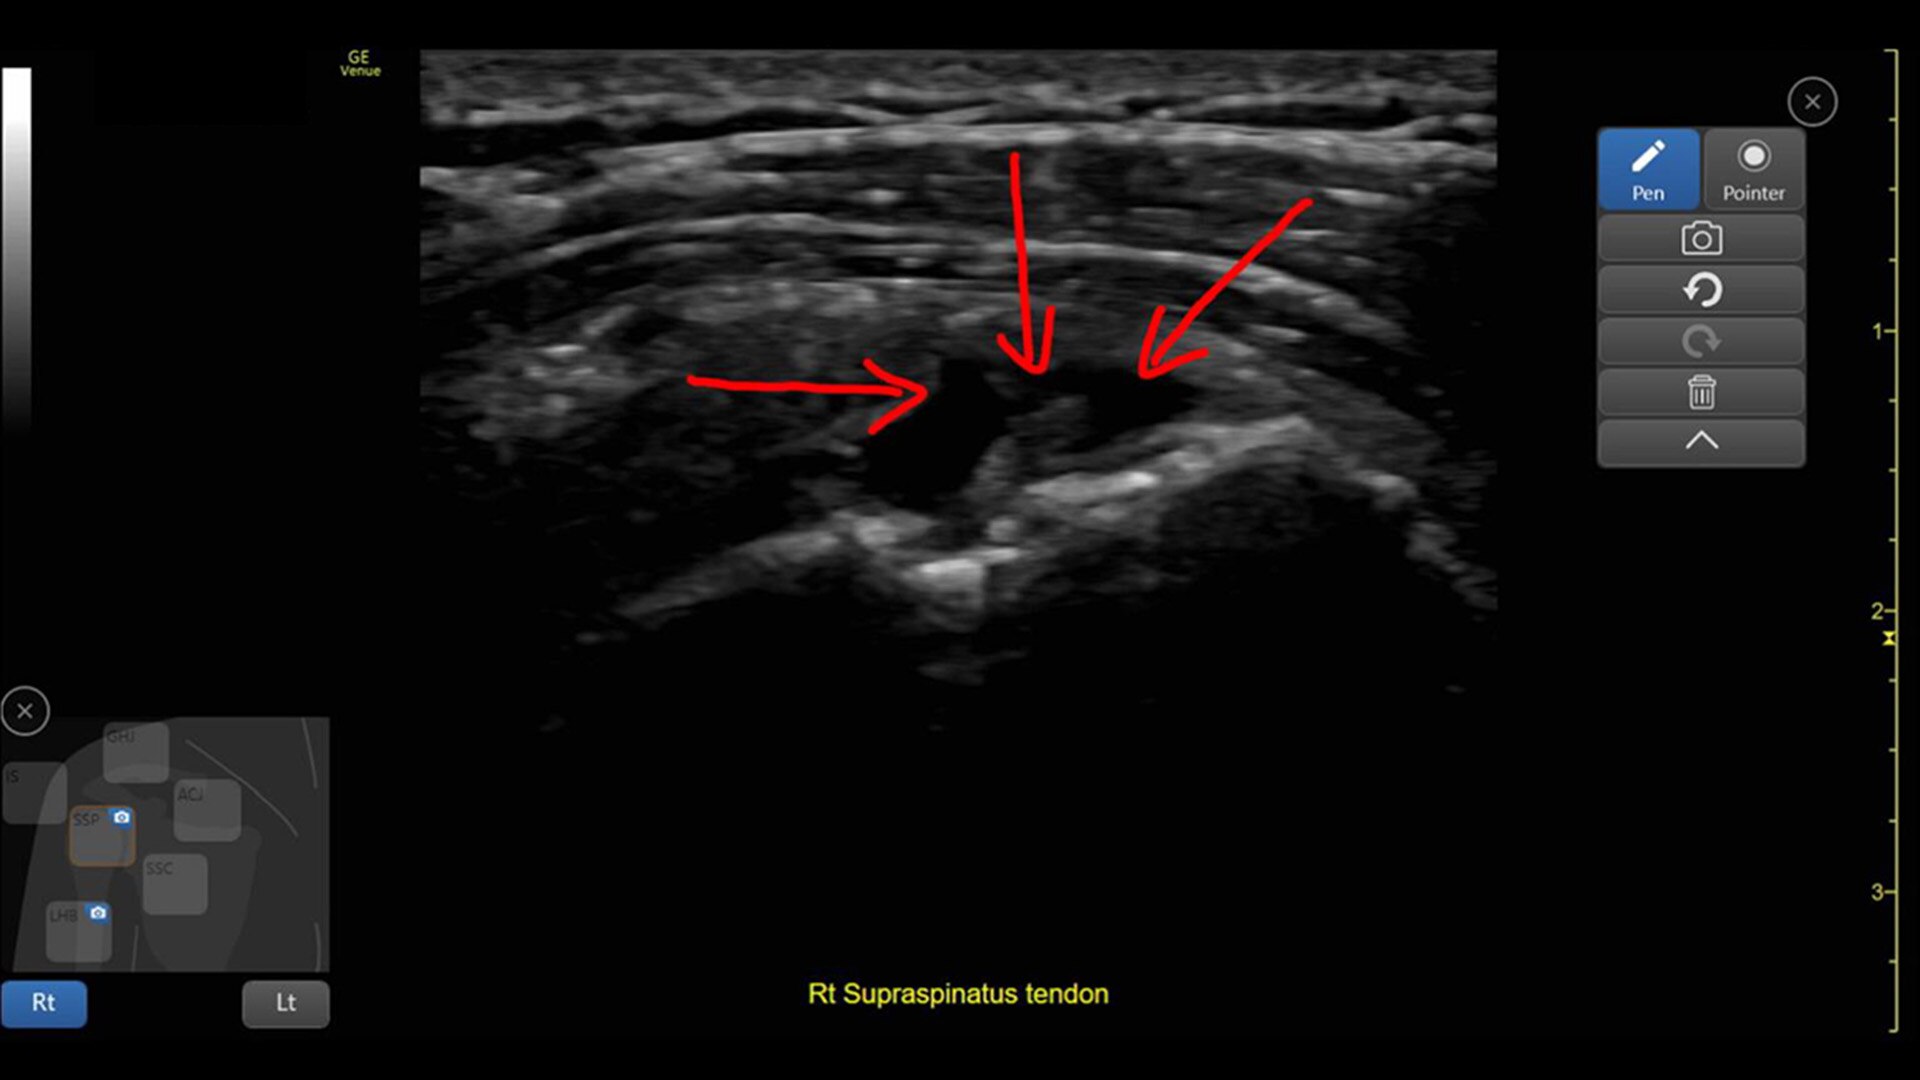

Created for Your Point of Care, the Venue Go™ ultrasound was designed for your needs and adapts for your challenges.

Its flexible design allows you to go from cart to table to boom with ease, providing your department with needed adaptability. AI-enabled tools help enable fast assessments, simplify the complex and support your life-saving decisions. Built with a small footprint and increased portability, Venue Go provides the flexibility you need to scan, diagnose and treat with ease and accuracy across a wide range of environments and care areas.

Venue Go provides the latest technologies to help deliver simple, fast, and precise solutions to the POCUS community.

Advanced and automated clinical tools enabling you to quickly diagnose, treat and determine a care pathway.

Venue Go has been designed and tested to be walk up easy for novice to expert users, and it features a number of AI-enabled automated tools to accelerate clinical workflow while also reducing the fatigue of repeated and difficult tasks. Utilizing proprietary algorithms, we synthesize data from numerous patients to ensure accurate calculations for clinical confidence.